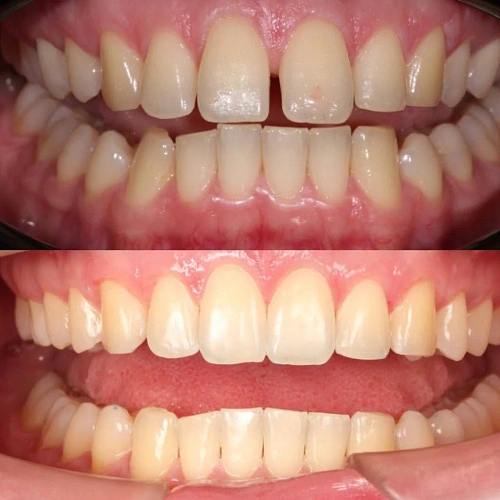

Нарушение соотношения челюстей и неправильное положение зубов — зубные ряды смыкались некорректно, зубы стояли со смещением.

Прозрачные элайнеры 3D Smile на обе челюсти. Выровнять зубы и нормализовать смыкание. Основной набор — 34 капы. Срок — около 2 лет.

Лечение заняло 32 месяца (февраль 2023 — октябрь 2025). Понадобился один дополнительный набор из 28 кап — итого 62 капы. Параллельно проводилась профессиональная гигиена.

Зубы выровнены, смыкание нормализовано. Установлены несъёмные ретейнеры на обе челюсти, сняты сканы для ретенционных кап. Консультация ортопеда запланирована на более поздний срок.

Проблема: Пациентку беспокоило неправильное смыкание зубов и их положение — ряды не сходились как нужно, зубы стояли со смещением. Это влияло и на внешний вид, и на то, как распределялась нагрузка при жевании.

Решение: Поставили прозрачные элайнеры 3D Smile на обе челюсти. Начали с набора из 34 кап, но в процессе стало понятно, что для полной коррекции нужна доработка — заказали дополнительный набор из 28 кап. Это нормальная ситуация: организм реагирует на перемещение зубов индивидуально, и заранее предсказать точное количество кап до последней штуки невозможно. В итоге 62 капы за 32 месяца — зубы встали на место, смыкание пришло в норму. Параллельно следили за гигиеной, чтобы дёсны оставались здоровыми на протяжении всего лечения.

Основной набор из 34 кап выполнил бо́льшую часть работы, но для финальной коррекции смыкания понадобился дополнительный комплект. Это не редкость — зубы двигаются с разной скоростью, и последние доли миллиметра часто требуют доработки. В итоге получили стабильный результат, который зафиксировали ретейнерами.